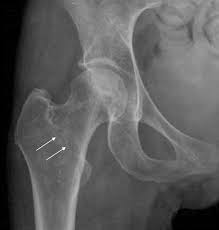

+ Atención de Fracturas y Lesiones Traumáticas:

Diagnóstico, reducción y tratamiento de fracturas, luxaciones y traumatismos óseos.

+ Prevención y Manejo de Lesiones en la Tercera Edad:

Detección y tratamiento de osteoporosis, caídas y otras afecciones comunes en adultos mayores.